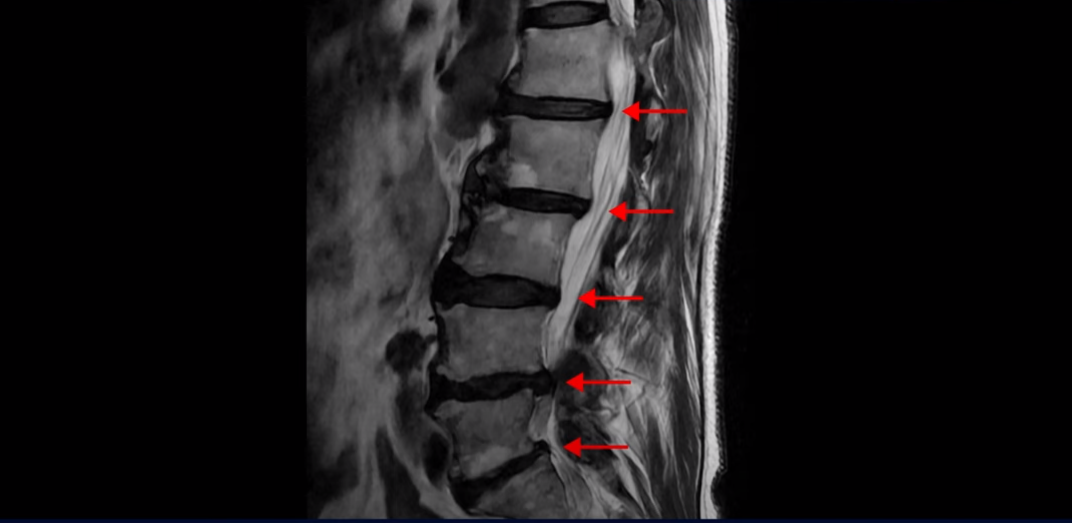

협착증은 노화 때문에 생기는 질환입니다. 나이가 들수록 노화와 퇴행 때문에 신경 구멍이 조금씩 좁아집니다. 이분도 신경 구멍이 좁아져 있습니다. 보시다시피 척추 여러 마디가 퇴행되어 있고

특히 왼쪽 신경가지가 빠져나가는 추간공들이 많이 좁아져 있습니다.

이분은 약 한달 전에 갑자기 왼쪽 다리를 아예 못 쓸 만큼 심하게 아프게 되었는데 허리를 펼 수도 없고 몇 미터 걸을 수도 없는 상태였습니다. 신경 주사를 여러 대 맞아도 전혀 듣지 않는 상태였는데 이분처럼 MRI 검사에서 신경구멍이 좁아져 있고 신경주사가 아예 듣지 않으면 십중팔구 수술하자는 얘기를 듣게 됩니다.

그런데 이분 신경구멍 좁아진 게 한 달 전에 갑자기 좁아졌을까요? 만일 1년 전에 전혀 안 아팠을 때 MRI를 찍었다면 최근에 아플 때 찍은 MRI와 많이 달라 보일까요? 정답은 거의 차이가 없다입니다. 아프기 전이나 아픈 후나 MRI로 보이는 신경 구멍의 크기가 같다면 그럼 왜 갑자기 한 달 전에 극심하게 아픈 증상이 생겼을까요? 그건 약해진 허리 주변 근육에 문제가 생겼기 때문입니다. 어떤 근육 문제가 이런 다리 방사통을 만들까요?